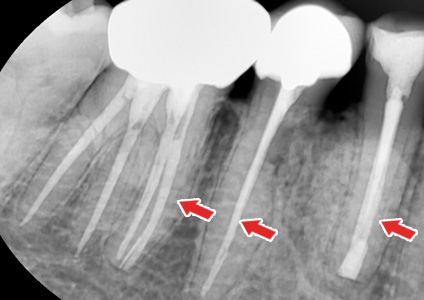

¡ã ½Å°æÄ¡·á¸¦ ÇÑ Ä¡¾ÆÀÇ X-ray »çÁø